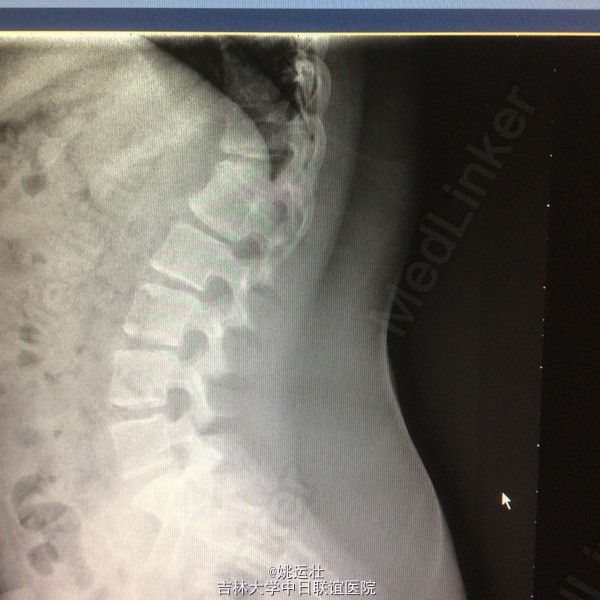

胸椎半椎体畸形 左侧第10肋骨缺如 隐形骶椎裂 双下肢膝外翻 双下肢肌挛缩症 脊柱畸形术,胸5、6、8、9腰1-2-3双侧椎弓根螺钉,去除胸11-12后方椎板,胸12半椎体及上下间隙间盘去除,椎间隙植骨。

本患者后凸可能是由于机制未明的神经肌肉病变,也可能是脊柱矢状位失平衡结果,若是前者导致可能会出现屈伸脊柱的平衡肌群肌张力或肌力增强或减弱,使融合后上下端再次出现冠状面或矢状面失平衡,需再次手术治疗,密切随访患者病情。